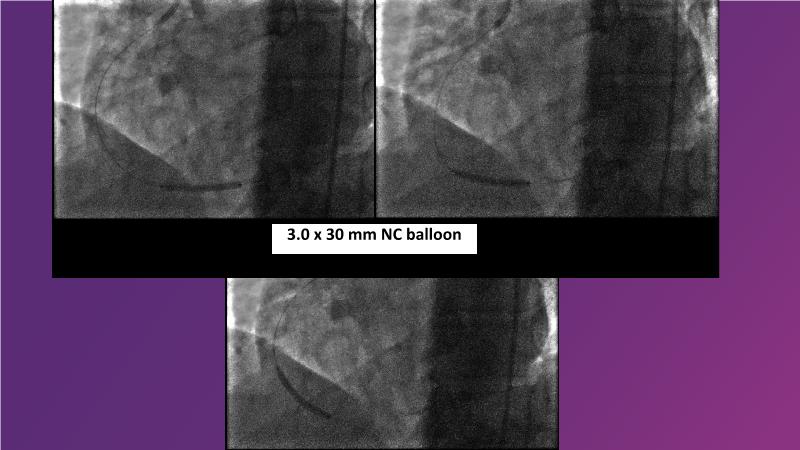

Browse this EuroPCR 2024 session to explore the safety and efficacy of sirolimus-coated balloons from pre-clinical data, review MagicTouch data from real-world populations with case-based examples, and learn about the MagicTouch sirolimus-coated balloon clinical programs. Discover insights and takeaways from the significance of the EASTBOURNE subgroups, and analyze the challenges and opportunities in PCI for diabetic patients.